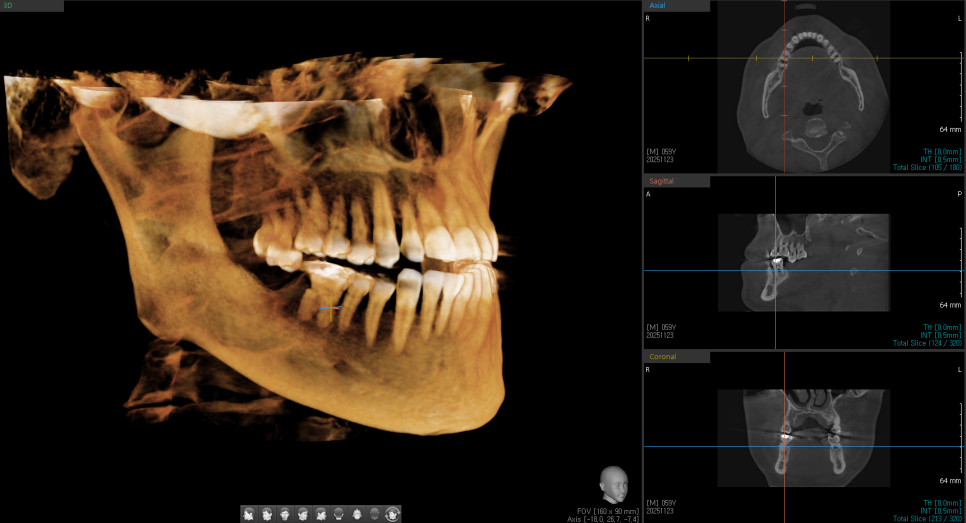

수술하기 전 사진입니다.

사진으로 봐도 오른쪽 윗니, 오른쪽 아래 어금니가 뿌리 주변이 많이 녹아있네요. 환자분은 오른 위 어금니 통증으로 내원하셨습니다.

다행히 골질이 좋아서, 발치 후 즉시 임플란트 식립을 진행했습니다.